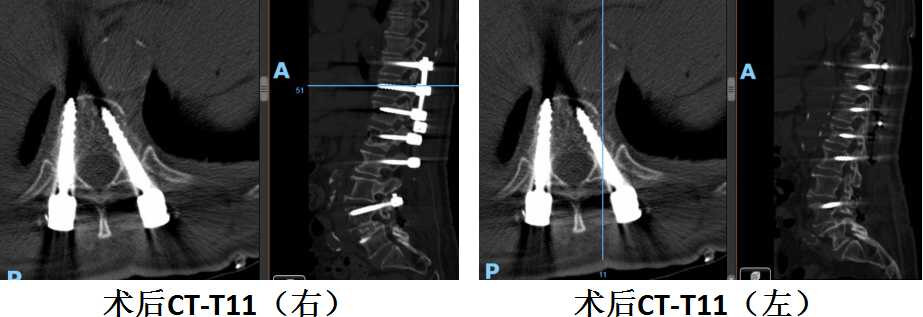

陈奶奶术后胸11水平螺钉位置良好